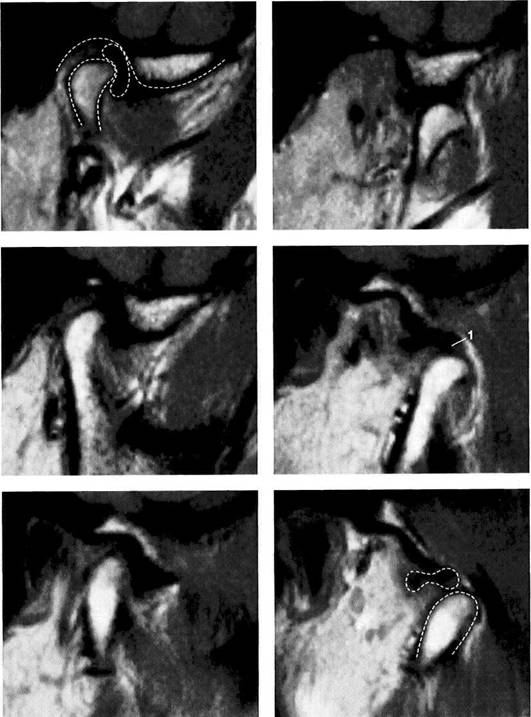

Normal joint

Left: Macroscopic anatomical pre­paration of a right temporo­mandibular joint with normal disk position. The pars posterior (1), pars anterior (2), pars media (arrow), and condyle (3) can be clearly seen.

Right: In spite of the reduction in signal caused by formalin fixation, the corresponding slice in MRI shows the identical relationships between the disk (1,2) and condyle

Medial disk displacement

Left: Formalin-fixed preparation from a right joint. In this anterosu-perior view, the displacement of the disk (arrows) toward the medial is evident.

Lateral pterygoid muscle

Lateral pole

Medial pole

Right: MRI in the angled coronal plane confirms the medial disk po­sition (arrows). The contours of the fossa and condyle are reproduced precisely.

Shape of the pars posterior

Left: Macroscopic anatomical pre­paration of a right articular disk showing its positional relationship to the condyle. The posteroinferior edge of the pars posterior (1) shows a small triangular area of fi­brosis (arrows).

Right: In spite of the sharply re­duced signal emission resulting from formalin fixation, even this type of change is accurately repro­duced (arrows). Here the use of a combination of T1 and T2 weight­ing is often helpful.

Reproduction of Anatomical Detail in MRI

Fibrosis of the bilaminar zone

Left: Formalin-fixed preparation of the centromedial part of a left tem­poromandibular joint with localized fibrosis of the bilaminar zone (ar­rows).

Pars posterior

Right: The MRI accurately repro­duces the abnormality (arrows) dis­tal to the flattened pars posterior. The contour of the condyle is indi­cated by a broken line.

Presumed "posterior disk displacement"

Left: Macroscopic preparation of a left temporomandibular joint with normal positioning of the pars an­terior (1) and pars posterior (2) in the lateral portion of the joint. The retrodiskal structures appear thick­ened.

Right: In an MRI there appears at first glance to be a posterior disk displacement (arrows). Under clos­er inspection, however, it can be seen that the pars anterior (1) and pars posterior (2) lie in correct rela­tion to the condyle.

Left: A view of the disk and the bil­aminar zone after further prepara­tion again reveals the correct posi­tional relationships. Here the pars anterior (1) and pars posterior (2) can be identified more readily. The presumed "posterior disk displace­ment" is a false positive interpreta­tion of the fibrosis of the bilaminar zone (arrows).

Right: MRI of the same joint shown in Figure 427.

Disk perforation and osteoarthrosis

Left: Anatomical preparation of a left temporomandibular joint with arthrotic changes (black arrows) and extensive disk perforation (white arrows). In the anterior re­gion only a part of the former pars anterior (1) can still be recognized.

Right: MRI shows similar conditions. The cortical layer of the arthrotic condyle is thickened extensively (arrows). The remainder of the pars anterior (1) can still be distin­guished.